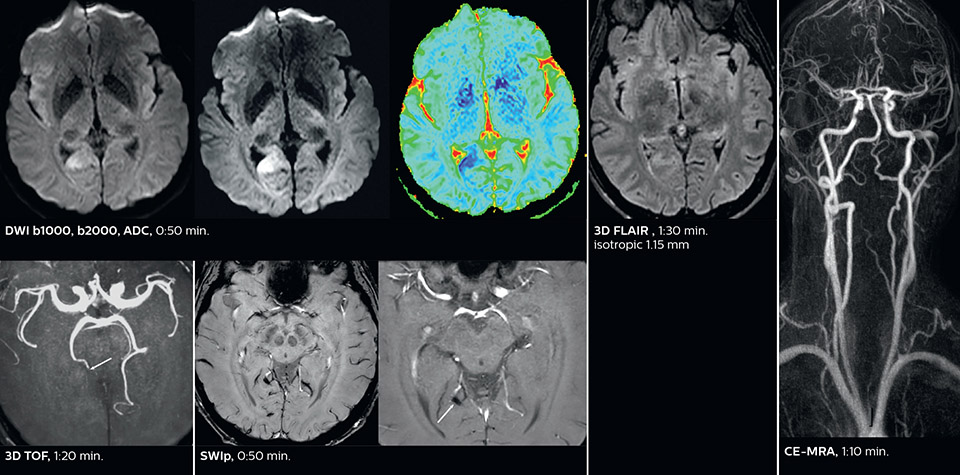

According to Dr. Savatovsky, Ingenia Elition has an impact in virtually all examinations. “We can either make the scanning faster compared to our older Ingenia 3.0T, or we save enough time so that we can add sequences we wouldn’t perform otherwise, or increase resolution. So, I think it has benefits for most of our patients.” “Some routine exams that we use every day have been shortened since we started using Elition. For example, we now use mostly a comprehensive stroke protocol (high b-value diffusion, fast 3D FLAIR, TOF, supra-aortic vessels angiography, SWIp, T1 post gad) that lasts 10 to 11 minutes, but our fast stroke protocol takes only 7 minutes. Our routine IAC needs about 10 minutes scan time and our comprehensive brain MS examination requires no longer than 13 minutes of scan time. Our ability to reduce acquisition times of most sequences helps to shorten total examination times, which in turn helps us to increase the number of patients we scan per day. “The main breakthrough for us was that Compressed SENSE and Multiband SENSE have allowed us to accelerate our examinations. Alternatively, we can invest the time gained in obtaining higher spatial resolution to see more details, or we can add additional sequences,” says Dr. Savatovsky. “That’s a big improvement from what we did before.”

Dr. Savatovsky appreciates the improvements and flexibility that Elition with Compressed SENSE and MultiBand SENSE provides, particularly for stroke patients. “For stroke, it allows us to cut about 5 minutes off of our stroke protocol, or to keep the same acquisition time and get more insights.” The ability to perform more sequences can help in making a swift and confident diagnosis. “For example, our stroke cases usually include the regular sequences that every center does (b1000 diffusion, FLAIR, time-of-flight angiography), but we also image supra aortic vessels, and we can replace a gradient echo sequence with a fast 50-second susceptibility-weighted sequence, and all of this doesn’t add much time. because all the regular sequences are accelerated on Elition.” “The time savings with Compressed SENSE and MultiBand SENSE make it easier to add sequences to give us additional insights. Depending on the context and the first results, we might add a DSC perfusion to assess the ischemic penumbra, an ASL perfusion to help find an alternative cause in case of normal diffusion, or add a high-resolution T1 sequence for a stroke patient, to quickly assess wall imaging in emergency cases. The additional sequences can help improve patient management, because we can already consider some alternative diagnoses if the morphological MRI is normal.”

Using MultiBand SENSE allowed the staff to improve their diffusion quality. “Our diffusion sequence was already fast before, about 40 seconds. Now with Elition, it still lasts 40 seconds, but we improved the spatial resolution by 0.2 mm and use high b-values to be more sensitive to visualize changes related to acute stroke,” says Dr. Savatovsky. “We now also developed a high resolution DTI sequence (1.3 x 1.3 x 2 mm) that can be reformatted and takes 2 to 5 minutes depending on the coverage. We use it every time we have a doubt, or when we expect the diffusion to be abnormal but don’t see that on the fast sequence. We occasionally spot small ischemic infarctions that would not have been visible with the regular diffusion sequence.”

This is an example of acute ischemic stroke with distal occlusion of the right posterior cerebral artery. Note the improved visibility of the ischemic territory on the diffusion weighted image with high b-value. The 3D FLAIR shows a distal PCA occlusion. The fast SWIp depicts the thrombus on the isolated second echo image. The total scan time (including SmartBrain, preparations and a fast 3D T1w TSE Gd) is 8:00 minutes.